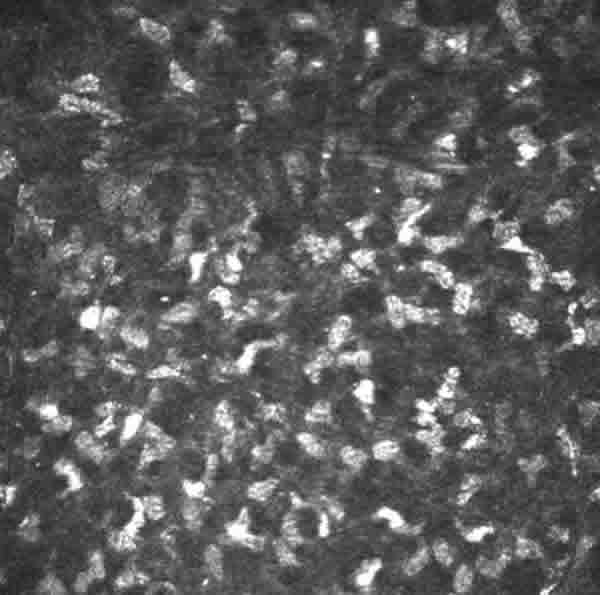

Estroma superficial: Alta concentración de núcleos de queratocitos hiper-reflectantes y rara vez ramificaciones nerviosas (fig. 7).

Fig. 7. Estroma anterior con abundantes núcleos de queratocitos.

Estroma medio: Menor concentración de núcleos de queratocitos (fig. 8).

Fig. 8. Estroma medio en el que disminuye el número de queratocitos con respecto

al estroma anterior.